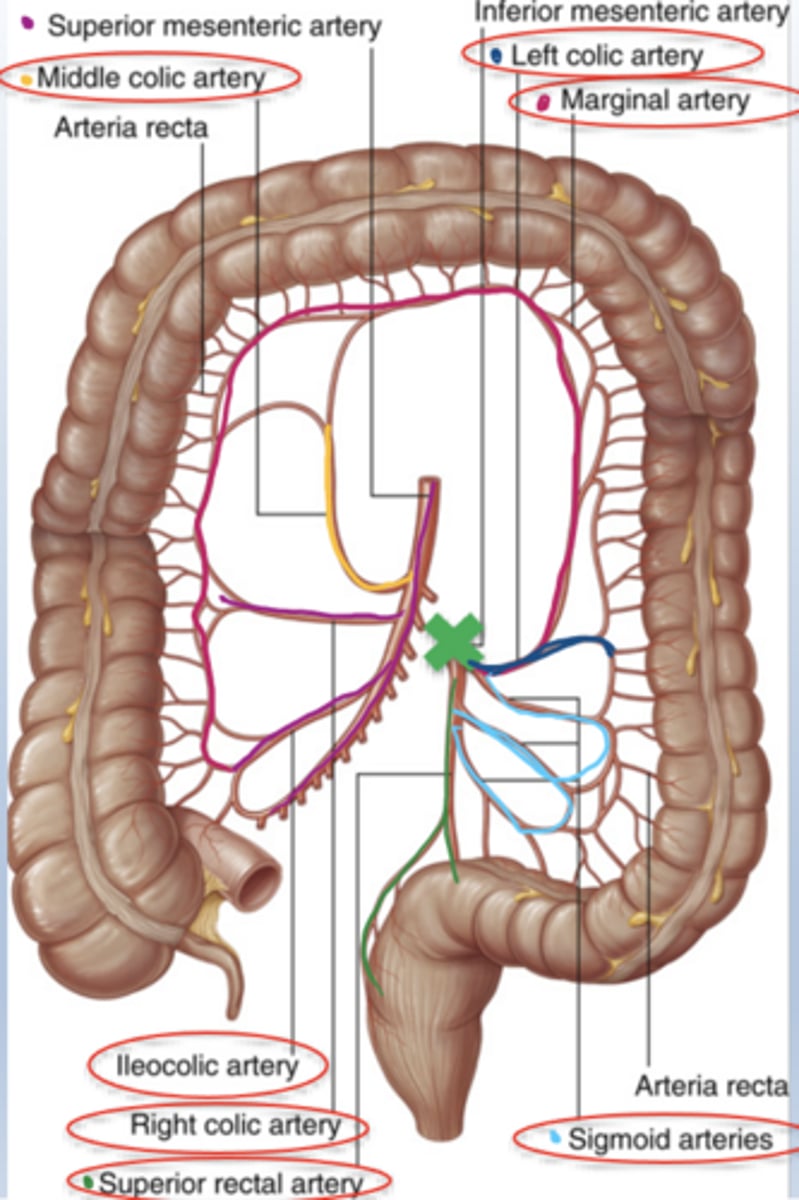

Which arteries supply the colon?

Branches from SMA and IMA depending on segment location.

Know the colonic vasculature

What does the middle colic artery supply?

proximal 2/3 of transverse colon

What does the left colic artery supply?

distal 1/3 of transverse colon and descending colon

What do the sigmoidal arteries supply?

sigmoid colon

What do the superior rectal arteries supply?

rectum

What does the marginal artery supply?

is a continuous arterial channel running along the inner border of the colon, supplies cecum to rectum

formed by connections between branches of superior mesenteric artery (SMA) and inferior mesenteric artery (IMA).

It acts as a collateral circulation pathway.